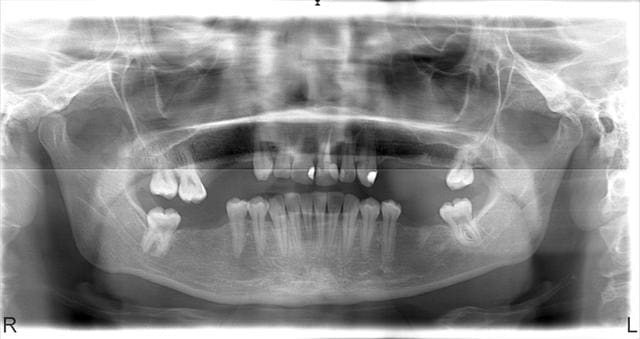

patiente de 28 ans

extractions effectuée il y a 8 ans (par un autre)

Migraine++++ depuis toujours sous traitement

envoyé par son Medecin qui estime que cela vient des dents

actuellement en cours d'assainissement paro

Et quest ce que tu comptes faire pour le Kyste en regard de 22 ?

si je vois bien il y a des racines qui trainent coté 47

pour la 47,il y a au moins une racine,c'est toi qui as besoin de lunettes,ou regarde la pano avec tes loupes ou ton beau microscope

ps si ce n'est pas une racine,il y a qd même une image suspecte ou un artefact,mais ce n'est pas net!

vers 36

ça au moins Athos,c'est une rectification justifiée,désolee,j'avais la tête à l'envers et me suis trompé de coté,effectivement cote 36,37